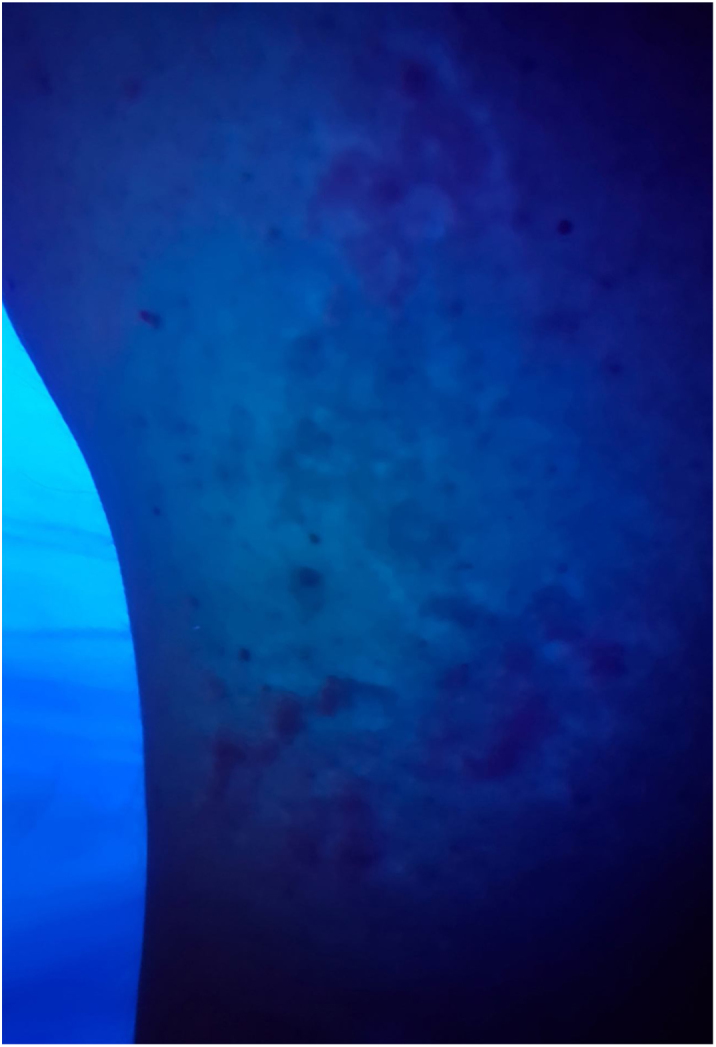

Figure 3.

Wood's lamp examination shows diffuse repigmentation pattern.